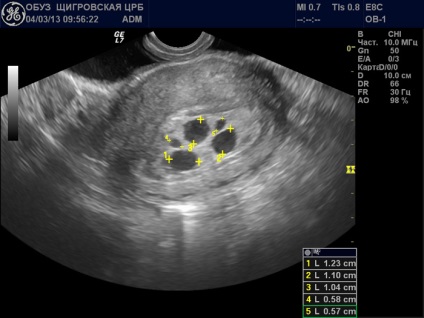

Ha egy nő aggódik a fenti tünetek, akkor forduljon orvoshoz, és mindent megmagyarázni neki. Végzett ultrahang, amelyben az orvos, és hiányzik az embrió vagy a felfüggesztés a fejlődés. És a tünetek hiányában a nők, ő megtanulja anembrionii a következő vizsgálat ultrahang készülék, ha az orvos észrevette a különbség a petesejt és embrió.